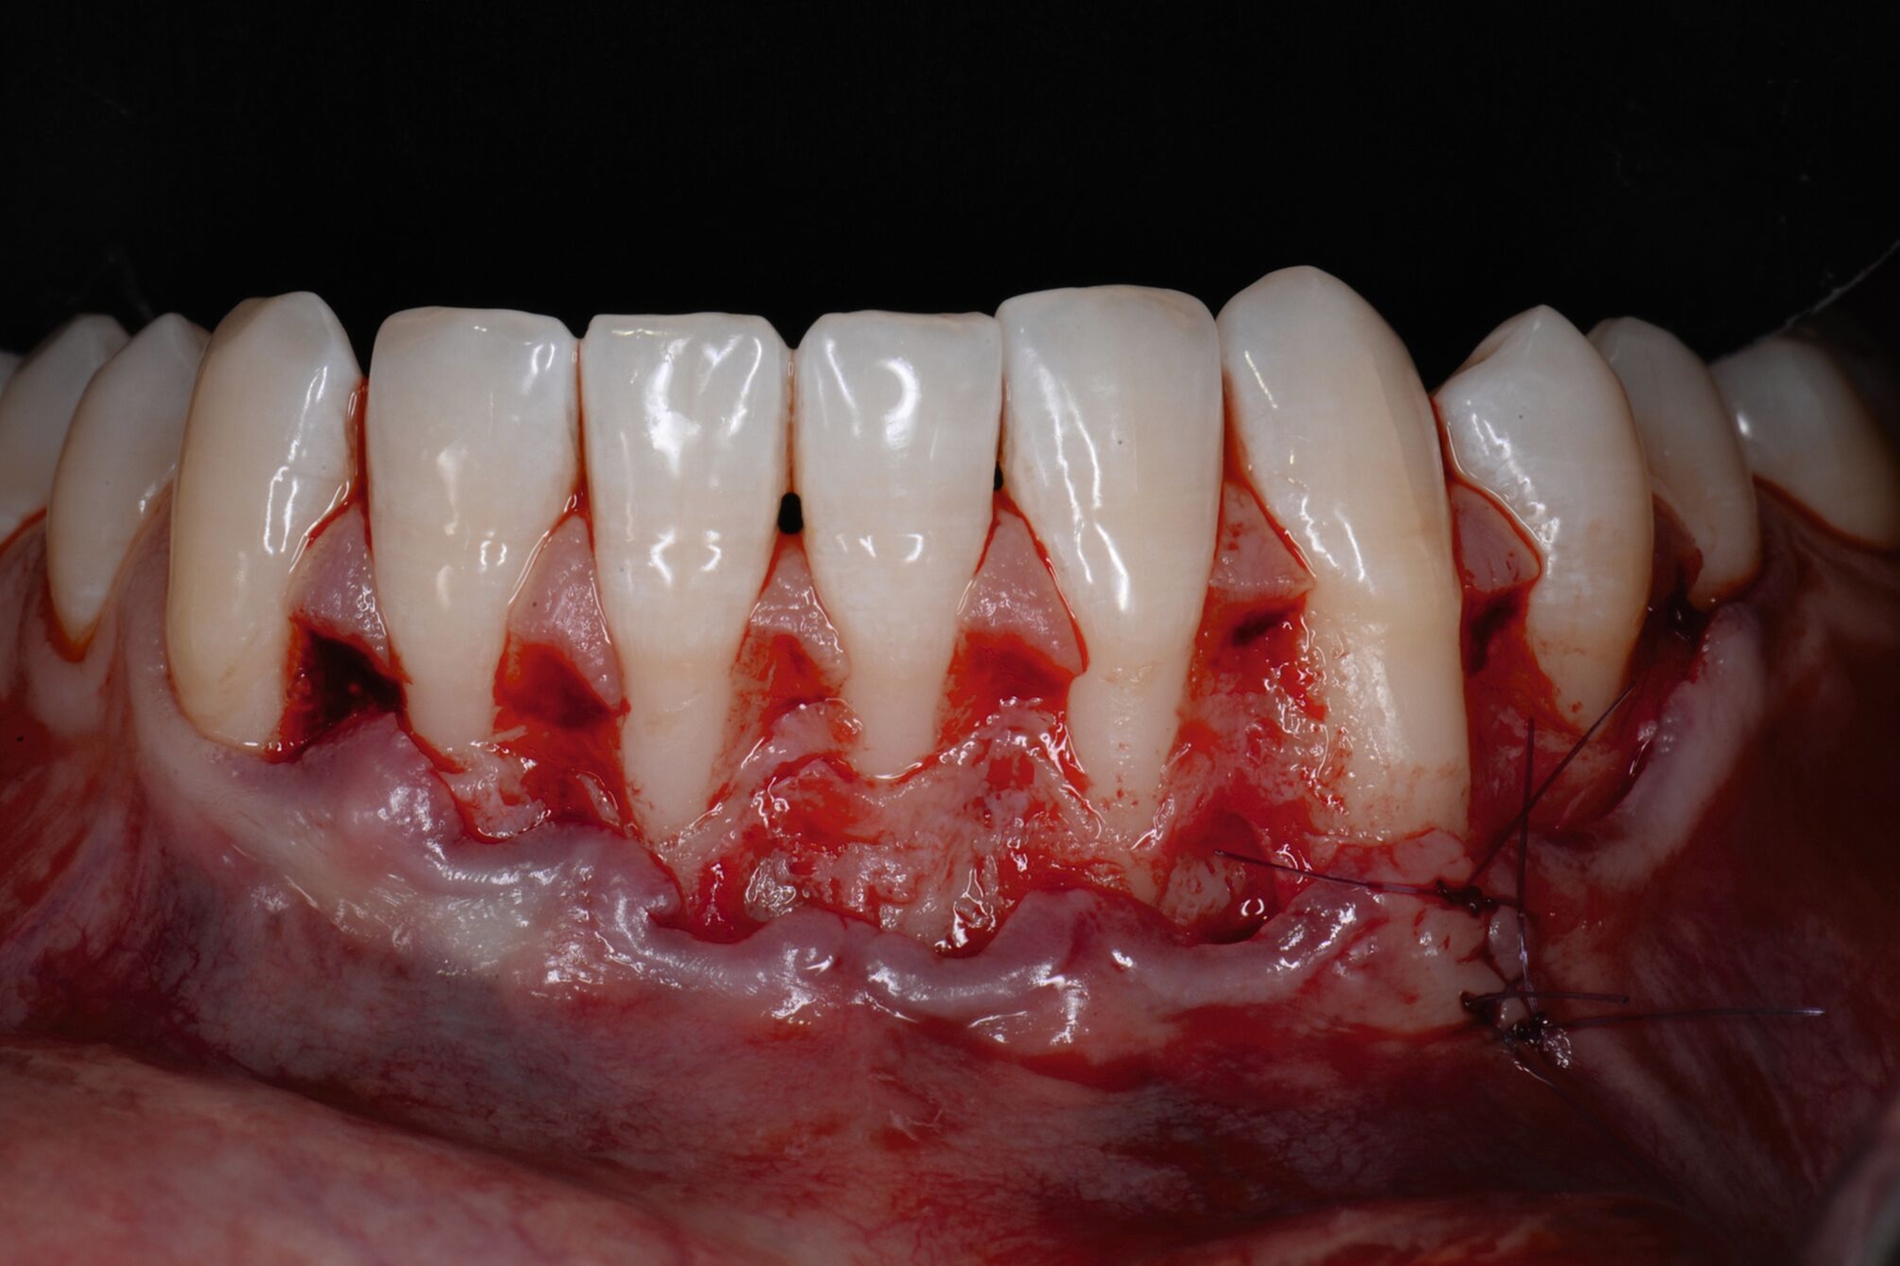

Das Vorgehen ist hier wie folgt: Zunächst wird im Bereich der tiefen Rezession der Gingivarand geringfügig exzidiert, um ein Zusammenwachsen der geschlossenen Lappenanteile zu ermöglichen. Anschließend wird der Schnitt in horizontaler Richtung durch leicht bogenförmige Schnittführungen auf Höhe der Schmelz-Zement-Grenze erweitert, um mindestens zwei Zähne rechts und links von der Rezession (Abbildung 3b). Im Unterkiefer-Frontzahnbereich, wo die Rezessionen heutzutage am häufigsten vorkommen, sollte der Lappen mindestens von Eckzahn zu Eckzahn gebildet werden, um ein harmonisches Ergebnis nach Abheilung zu erreichen. Auf vertikale Entlastungsinzisionen kann komplett verzichtet werden. Anschließend erfolgt die Lappenpräparation nach dem bereits für koronale Verschiebelappen gängigen Prinzip teilschichtig-vollschichtig-teilschichtig.

Die Papillenbereiche werden mit dem Skalpell scharf vom Periost abgelöst. Dann wird das Periost durchtrennt und bis zur mukogingivalen Grenze ein vollschichtiger Lappen gebildet. Nach Überschreiten dieser wird wieder zweischichtig präpariert. Hierdurch wird eine gute Mobilisation des Lappens erreicht, die eine ausreichende Koronalverschiebung ermöglicht. Entgegen dem in früheren Jahren propagierten komplett teilschichtigen Vorgehen, kann durch dieses Verfahren die Gefahr von Lappenperforationen signifikant gesenkt werden, da diese insbesondere im Bereich der mukogingivalen Grenze auftreten. Nachdem die Lappenareale mesial und distal der Rezession gelöst sind, können diese durch zwei bis drei feine monofile Nähte miteinander verbunden werden (Abbildung 3c). Sobald durch diese Naht ein zusammenhängender koronaler Verschiebelappen entstanden ist, werden die Papillenbereiche koronal des gebildeten Lappens entepithelialisiert. Nach Entnahme eines Bindegewebstransplantats oder entepithelialisierten freien Schleimhauttransplantats wird die Wurzeloberfläche mit EDTA-Gel konditioniert und anschließend werden Schmelz-Matrix-Proteine aufgetragen (Abbildung 3d). Diese bewirken die Bildung eines new attachment und fördern zudem die Wundheilung, was gerade bei den delikaten lateralen Verschiebelappen von Vorteil sein sollte [McGuire und Cochran, 2003; Almqvist et al., 2011; Thoma et al., 2011; McGuire et al., 2016]. Anschließend wird das Transplantat durch Nähte ausgehend vom oralen Papillenbereich fixiert (Abbildung 3e). Zuletzt wird der Lappen mit sogenannten doppelten Umschlingungsnähten im Bereich der Papille durch Zug nach koronal und oral fixiert, was eine perfekte Positionierung ermöglicht [Zuhr et al., 2009] (Abbildung 3f). Hierbei muss darauf geachtet werden, dass der Lappen die Schmelz-Zement-Grenze um mindestens 2 mm überdeckt, um eine hundertprozentige Wurzeldeckung erwartbar zu machen [Pini Prato et al., 2005].

Der Lateral Geschlossene Koronal Verschobene Lappen ermöglicht eine annähernd narbenfreie Deckung singulärer parodontaler Rezessionen durch Verzicht auf vertikale Entlastungsinzisionen (Abbildung 3g). Das Lösen der Papillen im Rahmen der Verschiebung ermöglicht eine deutliche Anhebung des Lappens und somit durch großzügige Überdeckung das Erreichen vollständiger Wurzeldeckungen. Durch den lateralen Verschluss im Rahmen der tiefen, über die mukogingivale Grenze hinausgehenden Rezession kann keratinisierte Gingiva im Bereich dieser hergestellt und eine übermäßige Mobilisation und damit Einschränkung des Vestibulums verhindert werden.